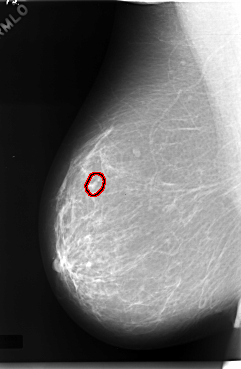

C_0057_1.RIGHT_MLO

FILE: C_0057_1.RIGHT_MLO.OVERLAY

TOTAL_ABNORMALITIES 1

ABNORMALITY 1

LESION_TYPE CALCIFICATION TYPE PLEOMORPHIC DISTRIBUTION CLUSTERED

ASSESSMENT 4

SUBTLETY 3

PATHOLOGY MALIGNANT

TOTAL_OUTLINES 1

BOUNDARY